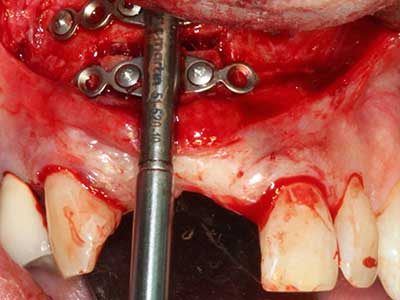

Indikation: Nervnahe Präparation

Wie bereits erwähnt lassen sich auch im Bereich der chirurgischen Zahnerhaltung Indikationsgebiete für die Piezochirurgie finden. Durch die Verwendung von speziellen Arbeitsspitzen wird die Darstellung der Wurzelspitze erleichtert, und gerade im unteren Prämolaren- und oberen Seitenzahnbereich lassen sich Nerven und Kieferhöhlenschleimhäute einfacher schützen. Bei undichtem apikalen Abschluss präparieren abgewinkelte Diamantspitzen zielgenau die Resektionskavität für das retrograde Wurzelfüllmaterial. Die Spitzen können durch die Ultraschalltechnik sehr grazil gestaltet sein, was Übersicht und Größe der Zugangskavität verbessert. So gehört in dieser Indikation die Anwendung der Ultraschallchirurgie zu den Standardverfahren der Wurzelspitzensresektion (Del Fabbro, Tsesis et al. 2010, Scarano, Artese et al. 2012).

Indikation: Wurzelspitzenresektion

Sollen chirurgische Eingriffe mit unmittelbarer Knochenbeziehung an empfindlichen Strukturen wie Blutgefäßen oder Nerven erfolgen, so bergen rotierende Instrumente ein erhebliches Potential an iatrogener Schädigung. Gerade bei Nervdarstellungen nach iatrogener Schädigung, oder aber im Zuge einer Nervlateralisation für resektive und rekonstruktive Eingriffe oder Implantatinsertionen können piezoelektronische Geräte hilfreich sein Knochendeckel zu präparieren und nervnahe Hartgewebsanteile zu entfernen (Abb. 17-20). Ein leichter Kontakt des Nervstrangs zur Piezospitze bleibt dabei in der Regel folgenlos – allerdings kann eine unvorsichtige Vorgehensweise mit sägeartigen Bewegungen bzw. Ansätzen bei noch vorhandener knöcherner Unterlage durchaus temporäre oder aber auch permanente Nervschädigungen verursachen. Das Risiko einer solchen Schädigung wird jedoch als wesentliche geringer eingeschätzt als unter Anwendung von Säge- oder Fräsinstrumenten (Pereira, Gealh et al. 2014).